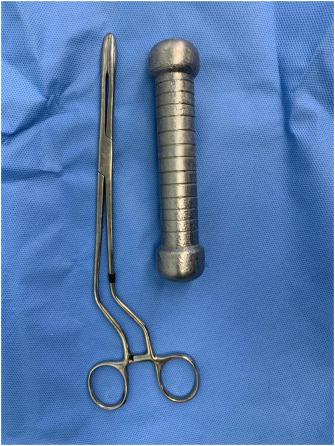

El equipo médico intentó extraer el objeto mediante el uso de anestesia y pinzas quirúrgicas, pero las mancuernas no cedían. Por lo anterior, uno de los encargados tuvo que proceder a una “extracción manual”, introduciendo su antebrazo en el hombre.